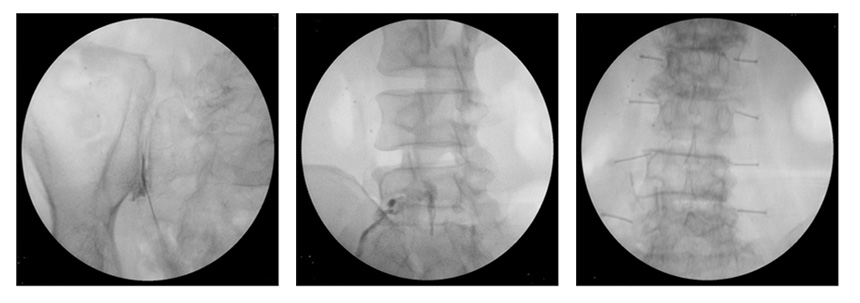

X선 투시촬영장치로 사용한 신경차단술 시술사진